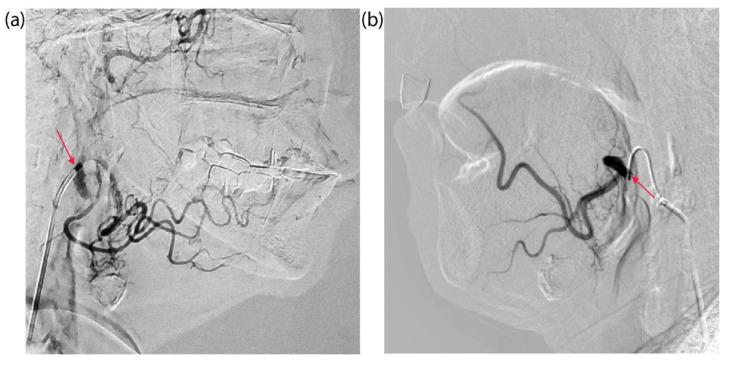

Despite advances in cancer treatment, head and neck squamous cell carcinoma (HNSCC) remains a serious clinical problem due to tumor aggressiveness, tumor resistance to therapy, and treatment toxicity. The combination of photodynamic therapy (PDT) with chemotherapy is a promising approach to improve efficacy while reducing side effects. For the first time, the possibility and antitumor effect of the combined use of PDT and chemotherapy with intra-arterial administration of chlorin e6 (Ce6) and cisplatin in patients with HNSCC were assessed. Two patients with locally advanced HNSCC received intra-arterial administration of Ce6 (at a dose of 0.5 mg/kg) and cisplatin (at a dose of 50 mg/m) via a catheter into the tumor-feeding artery followed by laser irradiation. Ce6 distribution, tumor response, and treatment efficacy were assessed by fluorescence diagnostics, confocal microscopy, and histopathological analysis. Intra-arterial administration of the photosensitizer (PS) and chemotherapeutic agent ensured high selectivity of their tumor accumulation. Fluorescence diagnostics showed rapid and selective Ce6 accumulation in the tumor and PS photobleaching after PDT. For a patient with three PDT sessions, there is a significant acceleration of the Ce6 spread from the tumor-feeding artery throughout the tumor bed with each therapy session. This is a good sign of a tumor stroma density decrease. The combined use of PDT and chemotherapy with intra-arterial administration of Ce6 and cisplatin is safe and feasible, with preliminary evidence of local cytotoxicity treatment for HNSCC, allowing targeted drug delivery to the tumor. This is the first report of the combined use of PDT and chemotherapy with selective intra-arterial administration of a PS and a chemotherapeutic drug for the treatment of cancer.

尽管癌症治疗取得了进展,但由于肿瘤的侵袭性、对治疗的抗性以及治疗毒性,头颈部鳞状细胞癌(HNSCC)仍然是一个严重的临床问题。光动力疗法(PDT)与化疗相结合是一种有望提高疗效同时减少副作用的方法。首次评估了在HNSCC患者中联合使用PDT和化疗并动脉内给予氯e6(Ce6)和顺铂的可能性及抗肿瘤效果。两名局部晚期HNSCC患者通过导管将Ce6(剂量为0.5mg/kg)和顺铂(剂量为50mg/m)动脉内注入肿瘤供血动脉,随后进行激光照射。通过荧光诊断、共聚焦显微镜和组织病理学分析评估Ce6分布、肿瘤反应和治疗效果。动脉内给予光敏剂(PS)和化疗药物可确保它们在肿瘤中的高选择性蓄积。荧光诊断显示PDT后肿瘤中Ce6快速且选择性蓄积以及PS光漂白。对于接受三次PDT治疗的一名患者,每次治疗过程中Ce6从肿瘤供血动脉向整个肿瘤床的扩散都有显著加速。这是肿瘤基质密度降低的良好迹象。联合使用PDT和化疗并动脉内给予Ce6和顺铂是安全可行的,有初步证据表明对HNSCC有局部细胞毒性治疗作用,可实现靶向药物递送至肿瘤。这是关于联合使用PDT和化疗并选择性动脉内给予PS和化疗药物治疗癌症的首份报告。